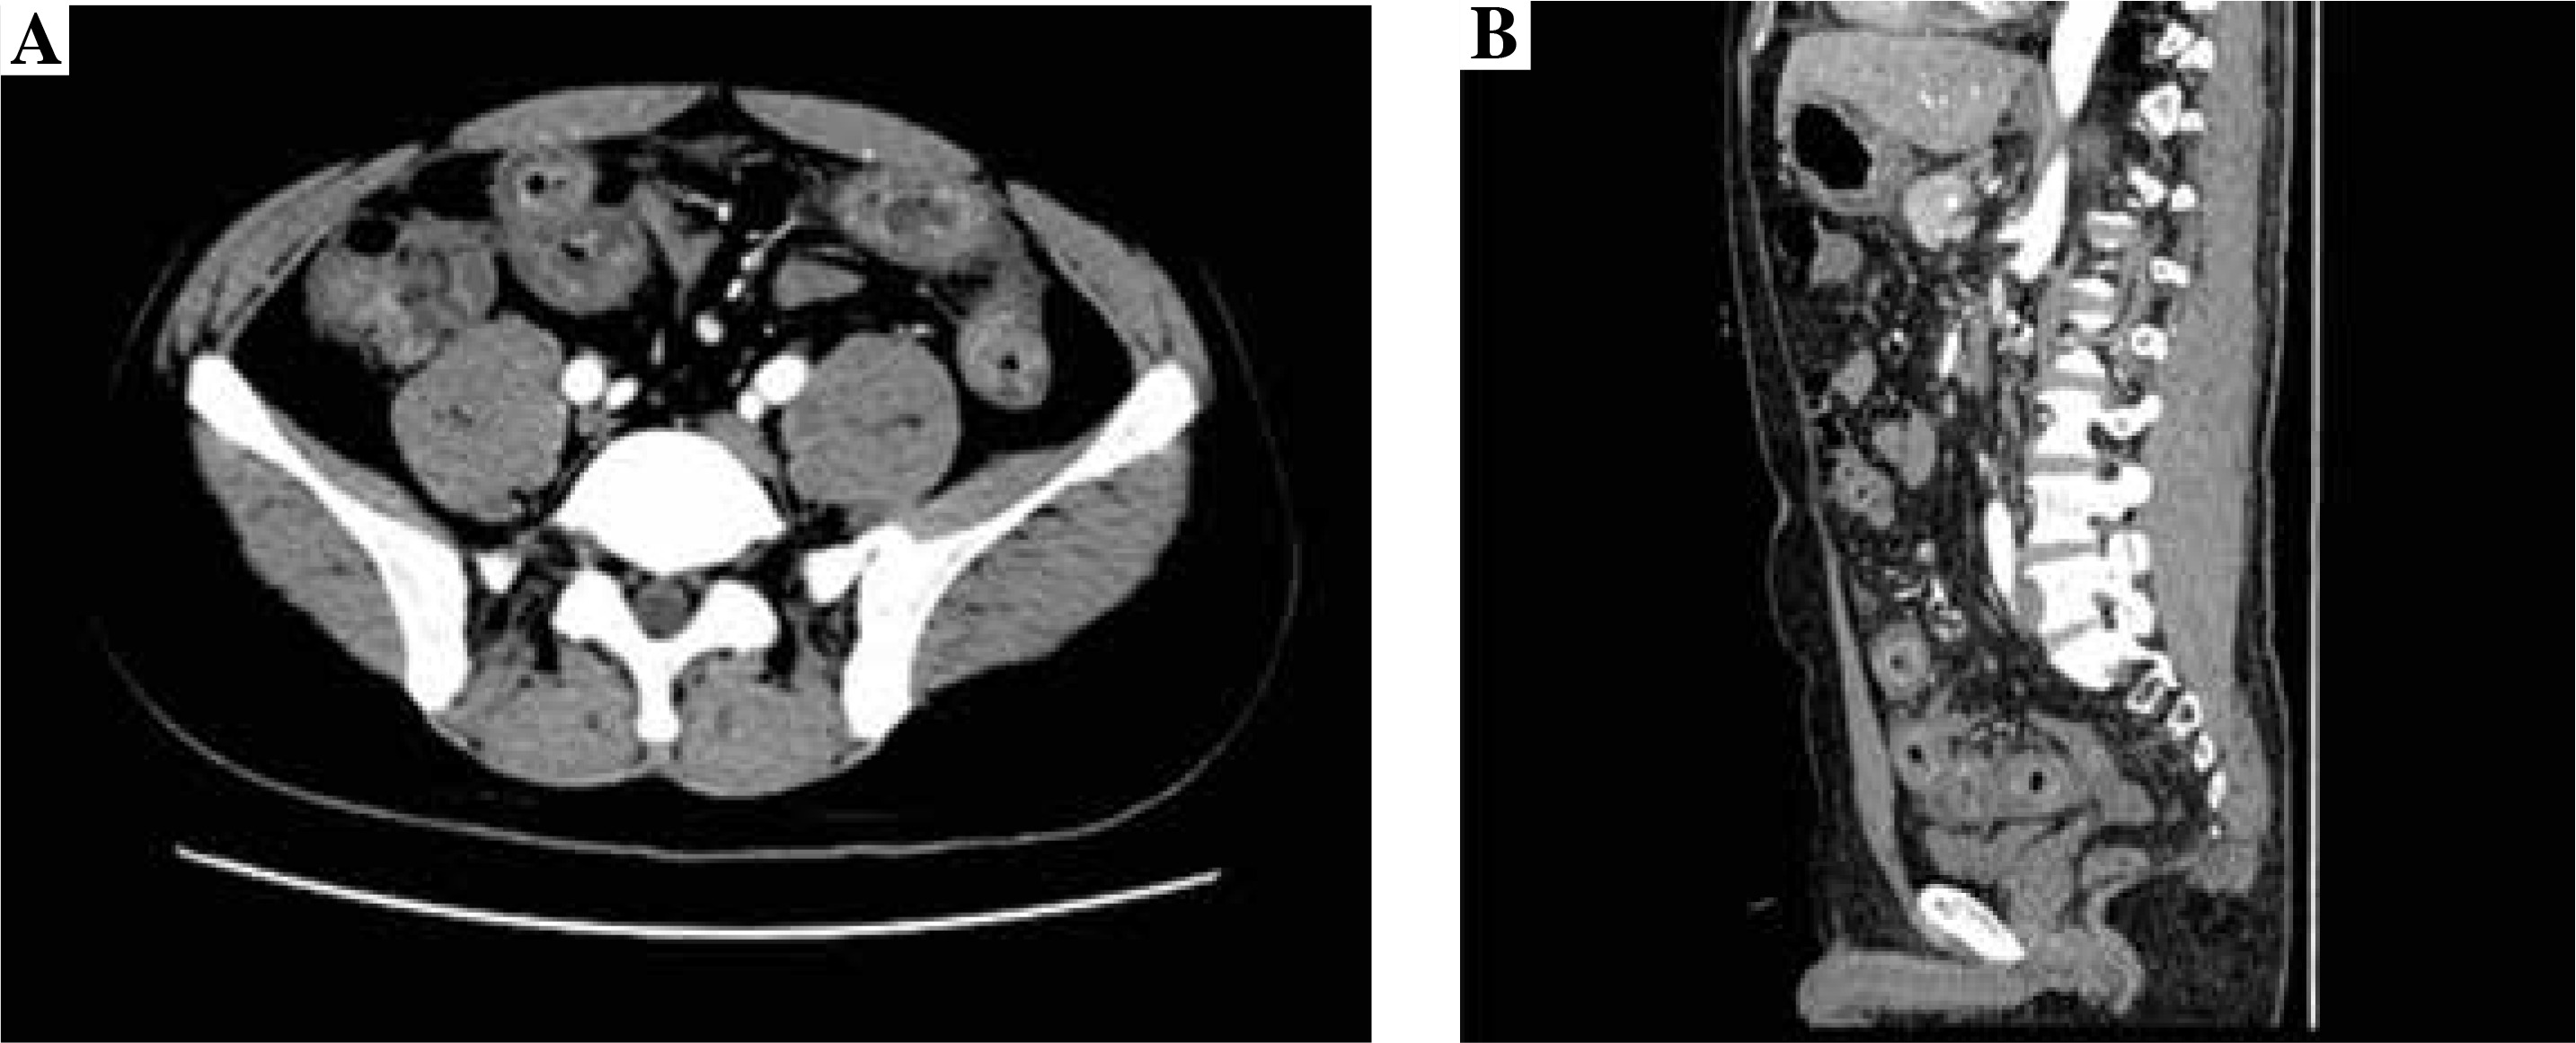

Abdominal contrast-enhanced computed tomography findings

The contrast-enhanced CT examination of the abdomen showed the intestinal canal wall thickening and edema (Fig. 2).

Therefore, we also conducted abnormal contrastenhanced CT and small intestinal enteroscopy for patients. The contrast-enhanced CT examination of the abdomen showed the intestinal canal wall thickening and edema. Endoscopic examination demonstrated diffused hyperemia, dropsy and erosion in the inferior segment of the ileum. And a ring-shaped ulcer was also seen in the small intestine. By combining the results of abnormal contrast-enhanced CT with small intestinal enteroscopy examination findings, we can diagnose the abdominal characteristics of patients.